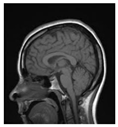

Table 1.

Results of marking and encrypting a medical image.

Table 1 shows the original image, marked image, encrypted image, the decrypted image, and the correlation between extracted blocks and original blocks after decryption using the Double Random Phase Encryption. It is clear that the encryption increases the security, and the mean correlation between the recovered mark and the original mark is measured to be 0.9 in both cases.

The PSNR and SSIM between the original image and marked image are 35.99 db and 0.97, respectively, which means that the marking does not affect the quality of the original image and keeps the invisibility of mark in the image. After encrypting the marked image using the DPRE algorithm, the results show that PSNR and SSIM between the encrypted and marked image are 12 db and 0.1, which verifies the strength of the suggested cryptosystem, as there is no similarity between them. Moreover, the results show that the correlation between the embedded rows and columns with the original is near to 1, verifying the robustness of the mark or signature.